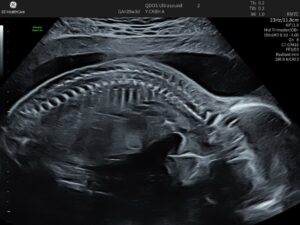

Generally performed between 19-21 week gestation, the scan ensures a comprehensive review of your baby’s development, including the skull, brain, face, chest, heart, stomach, kidneys, spine, limbs, and more. If you’d like, we can usually determine the baby’s sex at this stage. Additionally, we’ll check the amniotic fluid level and overall fetal proportions.

We approach the examination as a systematic check to make sure development is normal. We then consider what it will mean if the findings don’t align with expectations. The order of checks may vary due to fetal position and other factors, but consists of a series of working systems in the fetus. For instance, a normal amniotic fluid volume, reassures us that the fetus has a working urinary tract (even before we look at the kidneys and bladder). A normal-looking brain greatly reduces the chance of open spina bifida (even before we check the spine). If you have any particular concerns that we have not spoken of, please mention them.